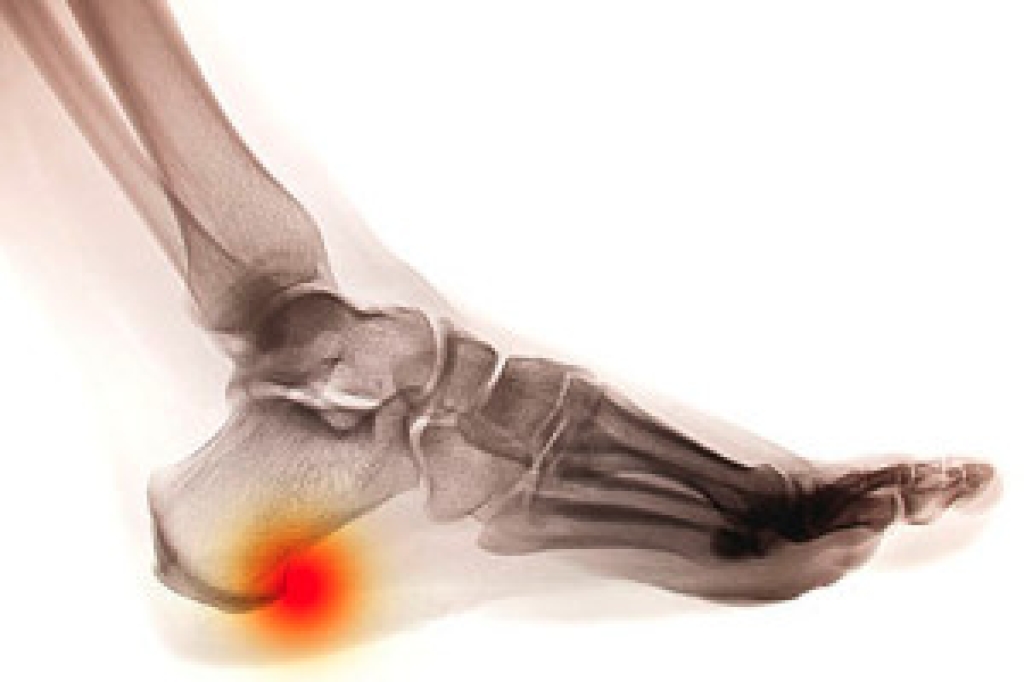

In many cases the cause of toe pain is obvious, but in others, a podiatrist may want to use more advanced methods to determine the problem. These can range from simple visual inspections and sensation tests to X-rays and MRI scans. Prior medical history, family medical history, and any recent physical traumatic events will all be taken into consideration for a proper diagnosis.

Treatments for toe pain and injuries vary and may include shoe inserts, padding, taping, medicines, injections, and in some cases, surgery. If you believe that you have broken a toe, please see a podiatrist as soon as possible.